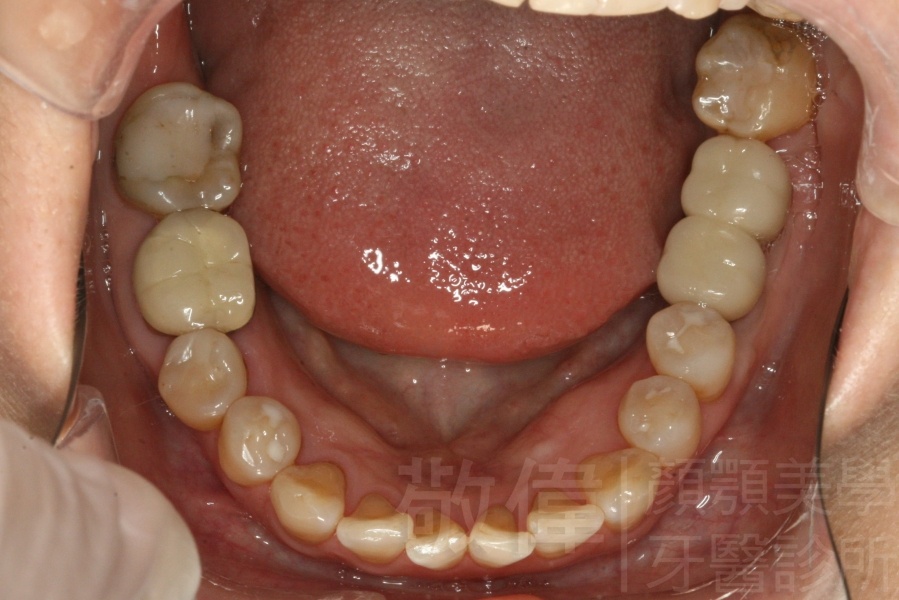

人工植牙/左下第1、2大臼齒植牙

治療前-下顎全口   治療後-下顎全口

治療前-缺牙區X光   治療後-大臼齒X光